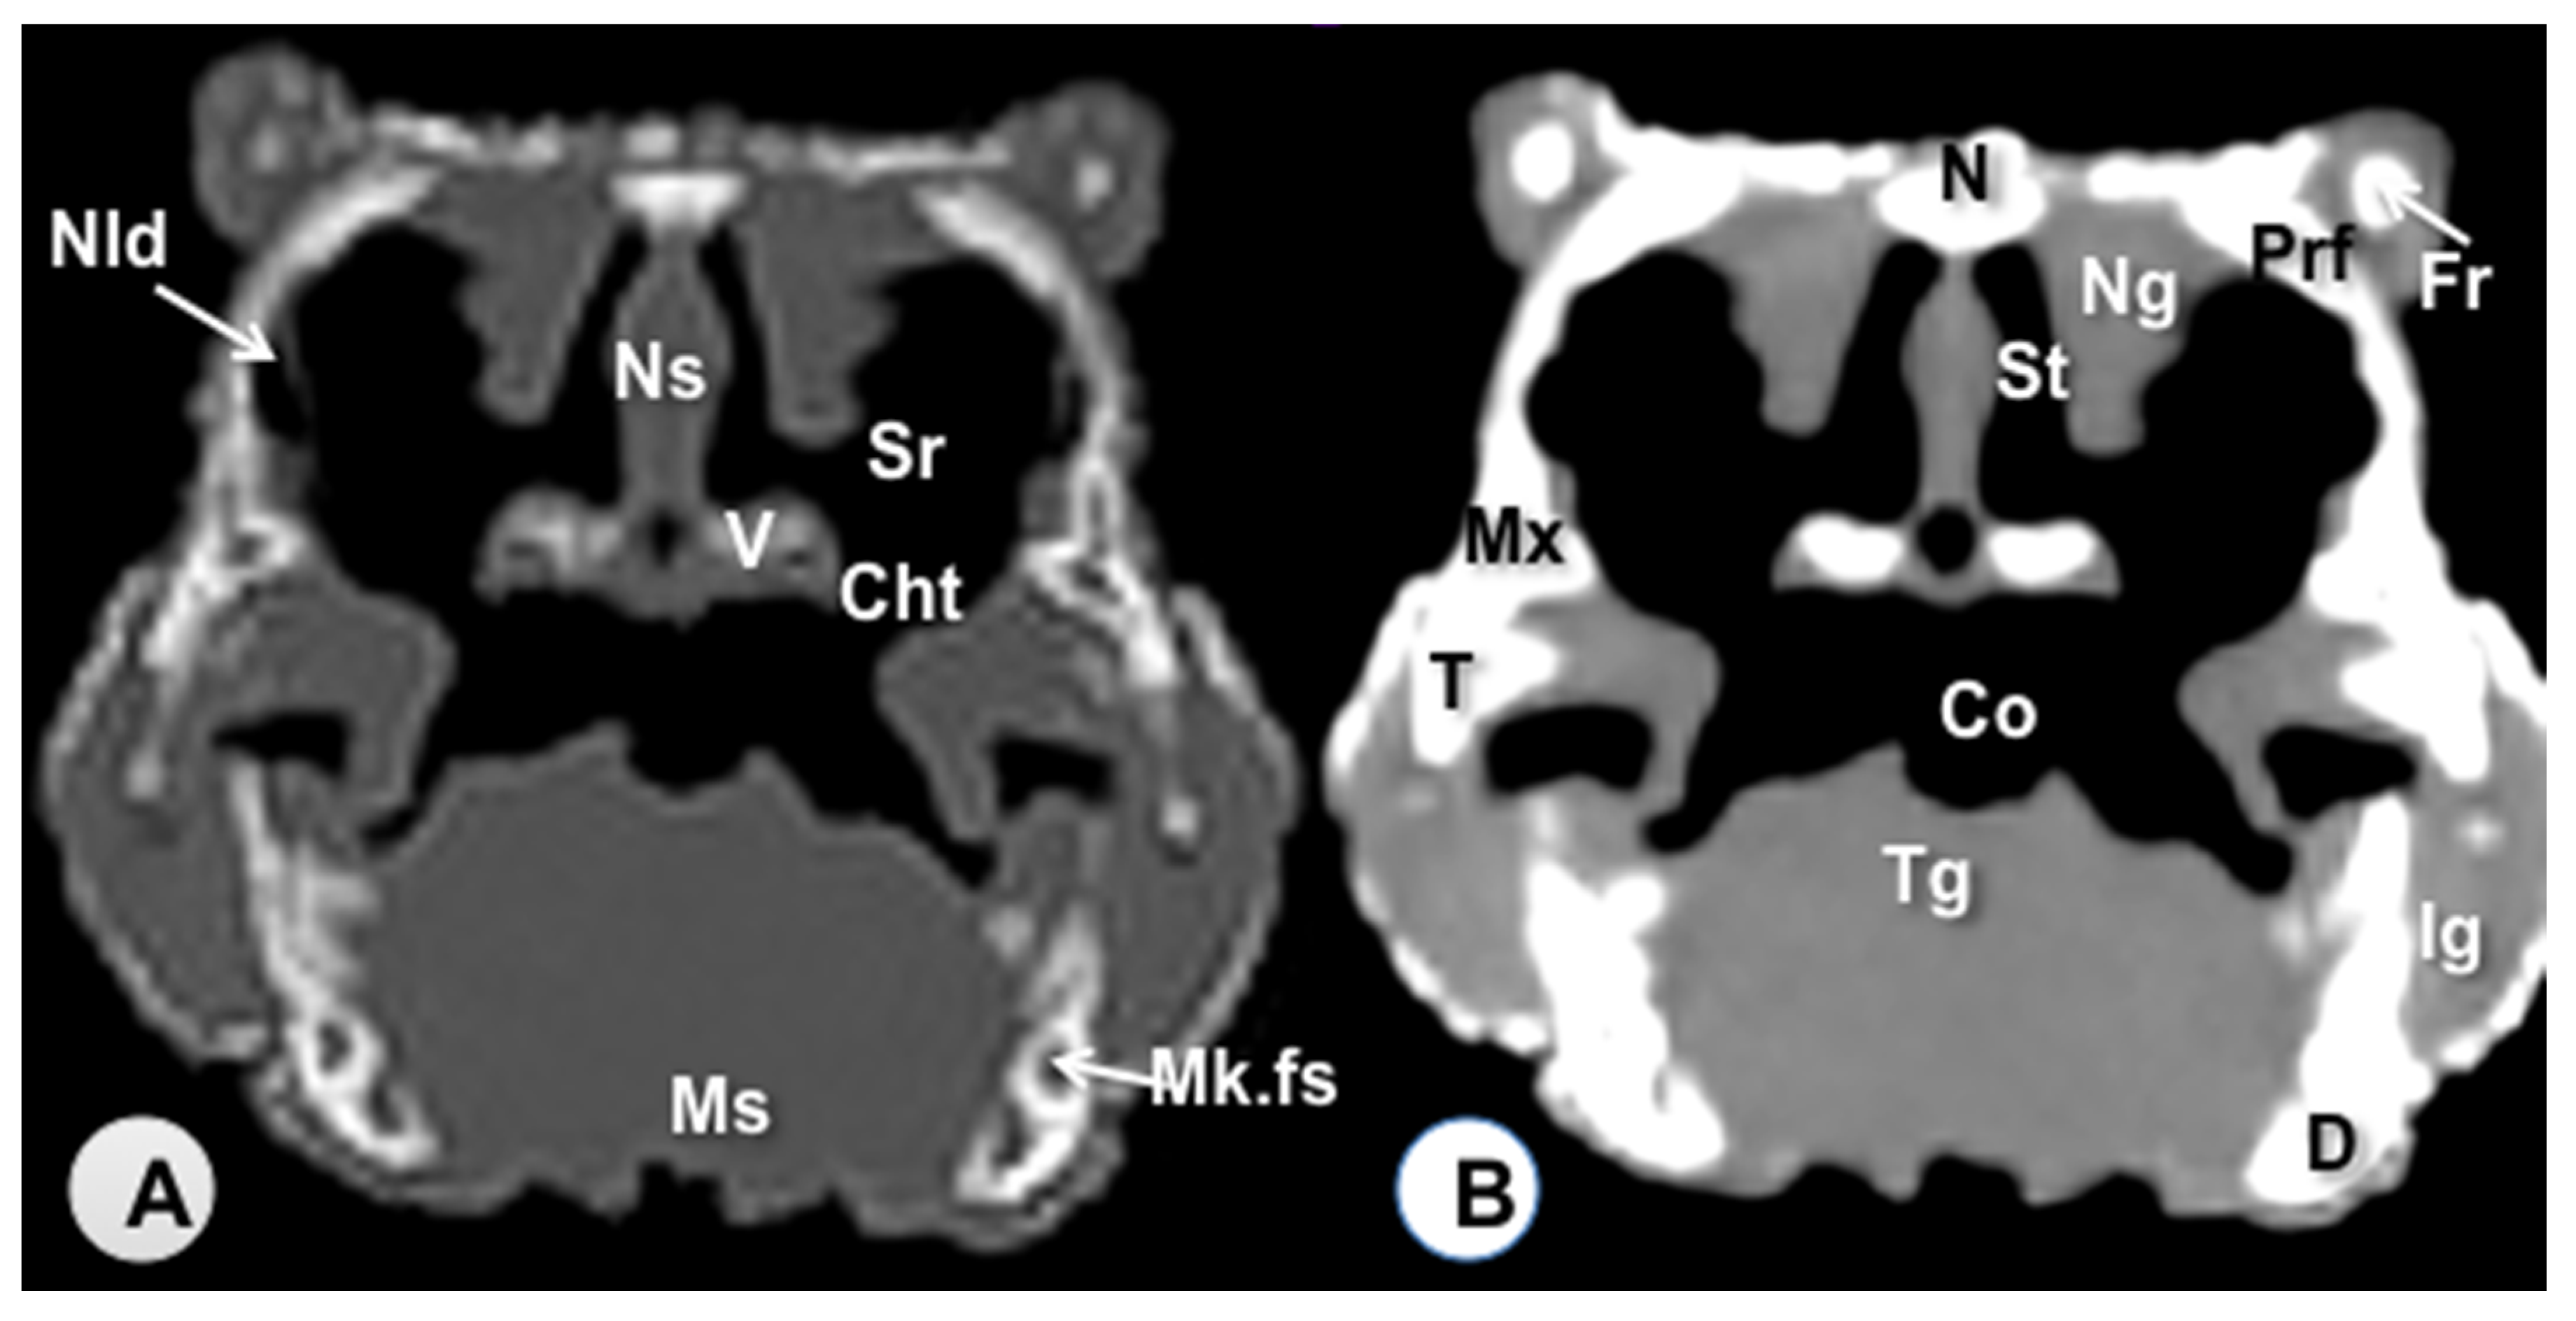

3.1. Transverse Computed Tomography Images